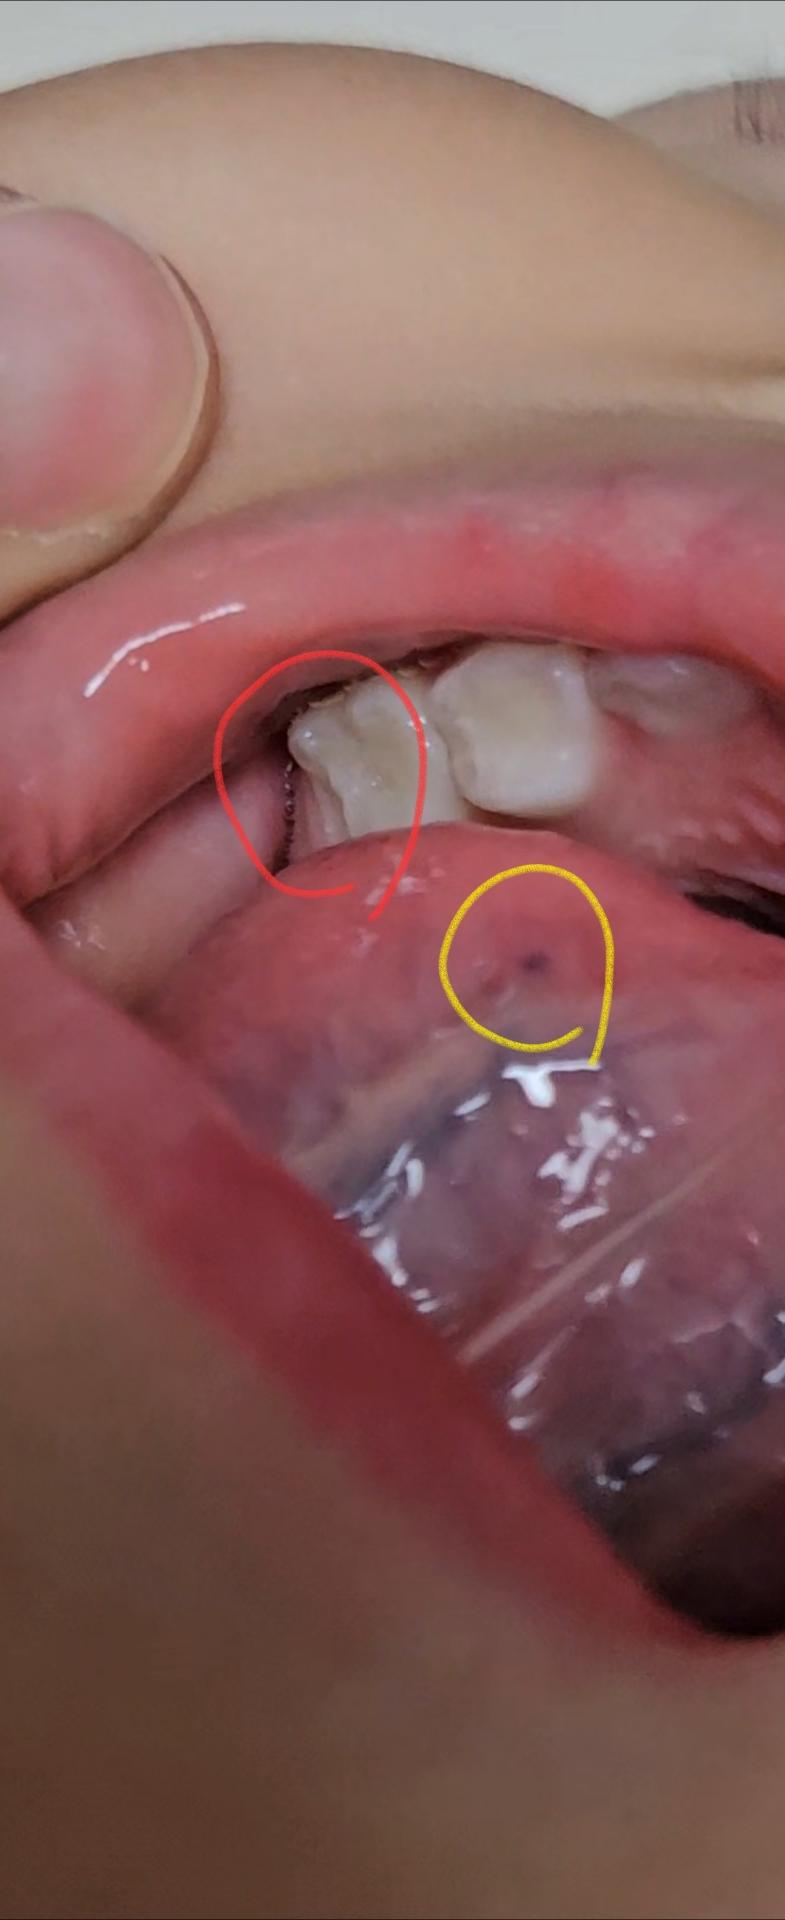

양측 상악제2유구치, 혀아래혈관 문의드려요.

1. 상악제2유구치 양측모두(빨간색동그라미) 사진처럼 치아가 자라는 모습처럼 보이는데 옆의 영구치가 나는건 아니죠?

2.혀아래 혈관이 분포되있다구 들었는데 노란색 동그라미부분은 혈관의일부 맞지요??

4세의 경우라면 아직 영구치가 나올 시기는 아니지만 약간 빠르다면 영구치일가능성이 잇습니다. 치과에 가셔서 파노라마 엑스레이를 찍어보세요. 사진에 보이는건 혀가 눌려서 생긴 피멍같습니다.

사진으로 보이는 부분은 혀 아래에 정맥혈이 지나는 부분입니다. 문제가 되는 것으로 보이진 않습니다. 해당 부위가 불편하거나 걱정이 된다면 치과에서 진료를 받아보는 것을 권해드립니다